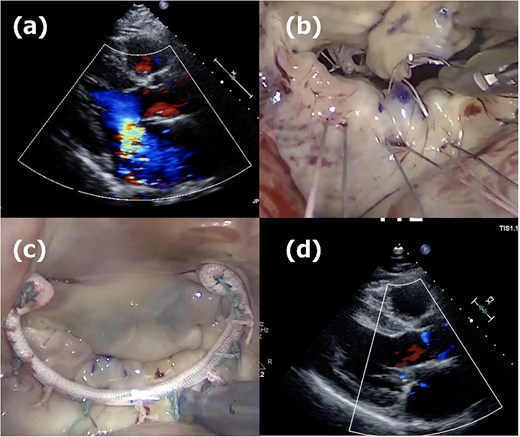

Second operation images. (a) Moderate mitral regurgitation caused by partial prolapse of the A2 segment, observed 3 weeks after the initial operation. (b) Intraoperative image showing the rupture of the ePTFE loop at the fixation site onto the leaflet during reoperation. (c) Three 20-mm long CV4 loops were attached to the posterior papillary muscle, and those loops were fixed to the A2 segment with CV4. (d) One week postoperative echocardiogram showing no residual mitral regurgitation after reoperation.

The second operation was performed 1 month after the initial operation. The approach employed was identical to that of the first operation; right-sided minithoracotomy was performed via the fourth intercostal space. Although access to the heart was more challenging due to adhesions, the operation proceeded in the usual manner, including femoral cannulations, aortic cross-clamping with antegrade cardioplegia, and right-sided left atriotomy. The most medial loop was ruptured at the fixation site onto the leaflet (Fig. 2b). The previously implanted annuloplasty band was removed, and three 20-mm CV4 loops were attached to the posterior papillary muscle and fixed to the A2 segment with CV4 (Fig. 2c). Thereafter, a new 34-mm annuloplasty ring (Physio II, Edwards Lifesciences, CA) was then implanted. Postoperative TTE confirmed no residual MR (Fig. 2d), and the patient remained free of recurrence at 1-year follow-up.